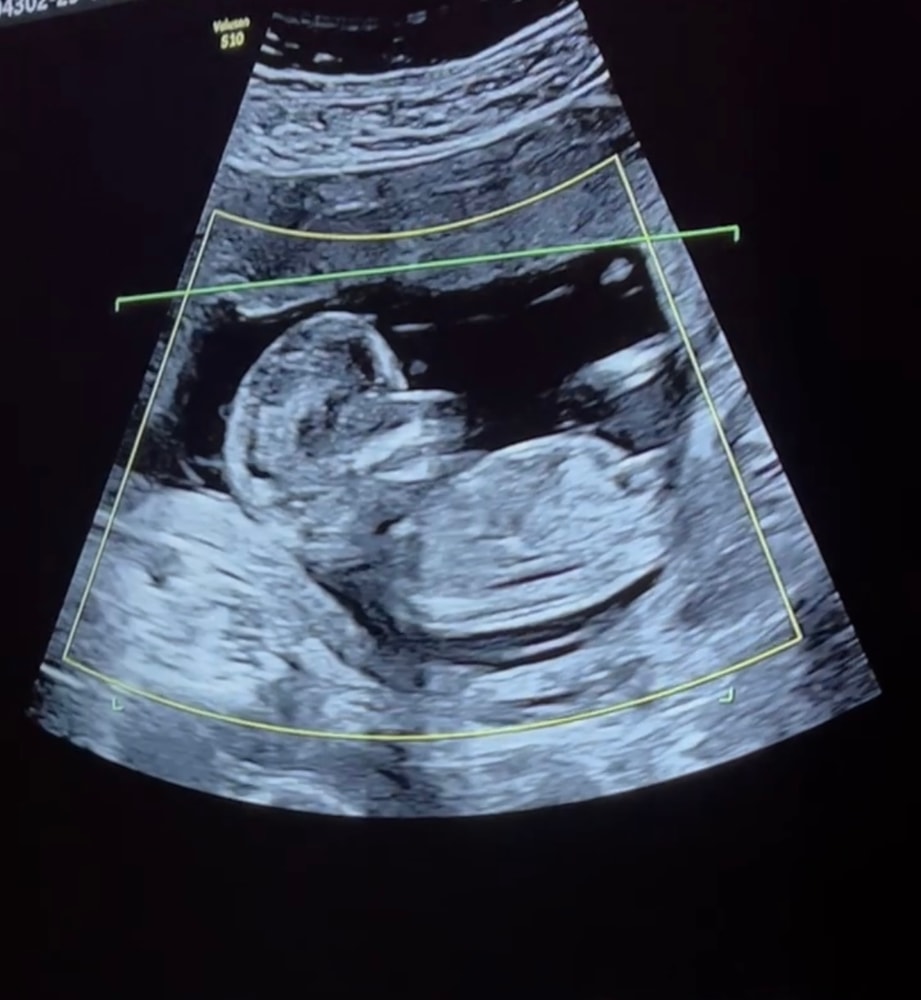

Вот и 22 недели 👀

Наши будни, наши неделькиПросто отметка для себя, вот уже и 22 недели по узи, как пишут, первый маленький ребенкин рубеж достигнут.

Пол до сих пор не знаем точно, только предположение с 1 скрининга на девочку, но через пару недель для себя ещё сходим на узи, может к Пятых смогу попасть. А то на 2 скрининге даже фото не дали🙄 Но муж уже по имени обращается, как к девочке 😁